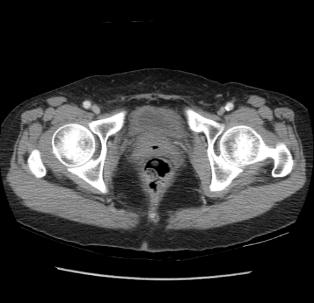

One hundred consecutive IC patients were investigated by symptom score, urodynamic study, cystoscopic hydrodistention, and bladder CT study. The BWT is divided into smooth (n=49), focal thickness (n=15), and diffuse thickness (n=36) subtypes, which are demonstrated in Figure 1.

Figure 1. Subtypes of BWT demostrated on CT